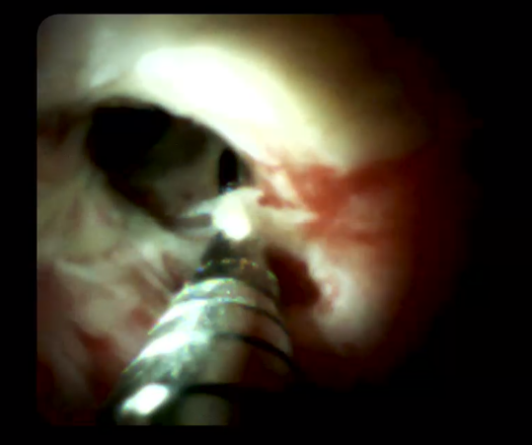

另外,經(jīng)口膽道子鏡光纖直視系統(tǒng)(SPYGLASS)是一種電子膽道子鏡,可通過(guò)十二指腸鏡到達(dá)膽管或胰管內(nèi),對(duì)病變進(jìn)行直視觀察,高清高分辨率顯示病變、并精準(zhǔn)指導(dǎo)活檢,對(duì)于膽胰管狹窄的診斷治療具有重要意義。

5466bc1aa2b44eeabb2f6ab4904c0f6c.Png  0c9bb25f31ed492197b787eecbde3974.Png

經(jīng)口膽道鏡下膽總管碎石